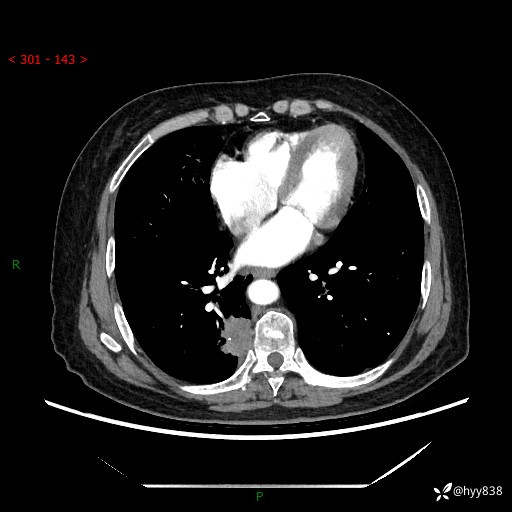

增强动脉期+静脉期

两期CT值:55Hu 53hu